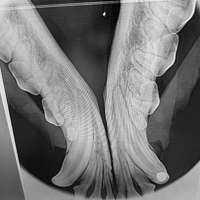

Eine umfassende und tiefgreifende Diagnostik ist auch in der Tiermedizin das A und O des Heilungserfolges. Nicht immer genügt eine allgemeine klinische Untersuchung, ein Tier zu begutachten, um eine eindeutige Diagnose zu stellen. Manche Symptome lassen kein eindeutiges Urteil zu, so dass wir in diesen Fällen auf bildgebende Verfahren wie Sonografie und digitales Röntgen zurückgreifen. So können Diagnosen schnell, konkret und direkt vor Ort in unserer Praxis erstellt werden.

- Digitales Röntgen